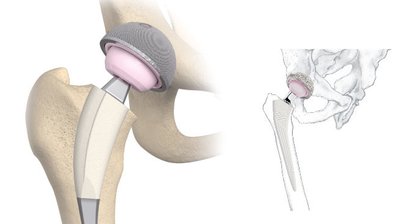

Wenn ein chirurgischer Eingriff notwendig ist, so finden Sie in mir einen Spezialisten für Operationen an Hüfte, Knie und Schulter sowie im Hand- und Fußbereich. Dabei setze ich auf schonende minimal-invasive Methoden.

Hüftprothese